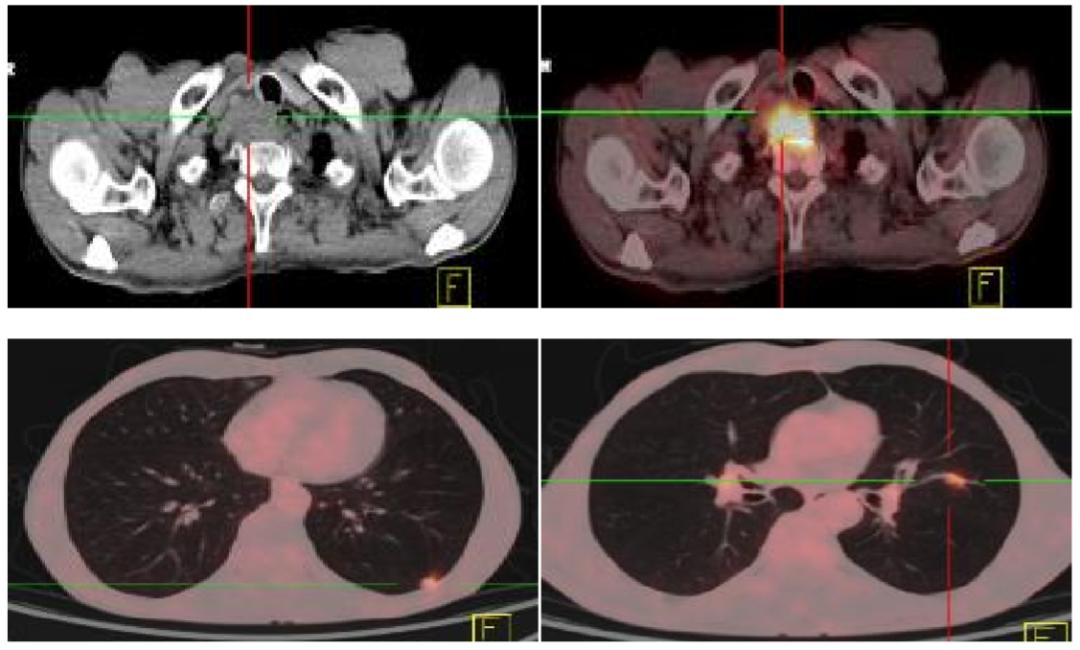

5.PET-CT(2017.09.11)

右侧颈部不规则软组织肿块代谢活跃,符合恶性病变,考虑食管来源伴周围淋巴结转移可能性大;双肺多发高密度结节代谢活跃,考虑转移。